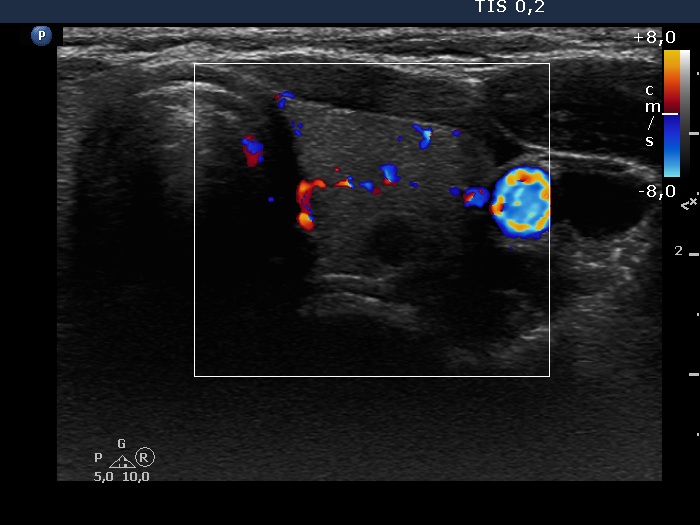

Consecutive patients with Hashimoto's thyroiditis - Case 26. (ultrasonographic picture 6)

Left lobe, horizontal scan, color Doppler mode. The vascularization is average.